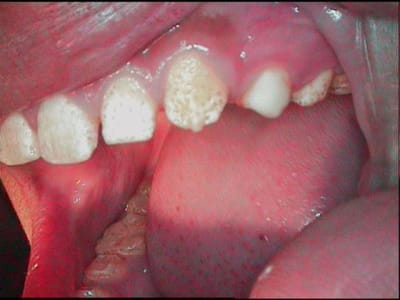

ce matin, comme la sensibilité résiduelle etait tres légère, j'ai osé sur 23

23 fflmpl - Eugenol